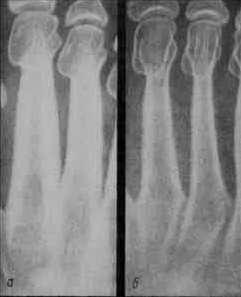

6.Образование вторичного центра окостенения в эпифизах по типу эндохондрального.

Рост кости: в длину – с помощью метафиза,

в ширину аппозиционно.